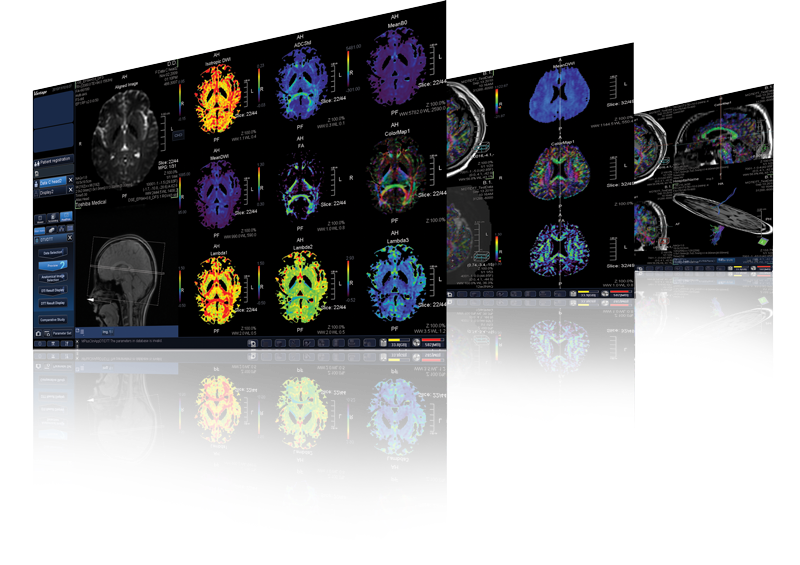

M-Power™

Розширені можливості програмного забезпечення, щоб робити більше.

M-Power було створено технологами для технологів. ЇЇ інтуітивний інтерфейс спрощує робочий процес та постпроцессинг до трьох кроків 1, 2, 3.